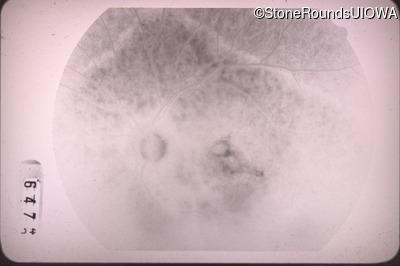

Fluorescein Angiography - Right - 20/100 -1

Exemplar

Fluorescein Angiography - Left - 20/40 -1